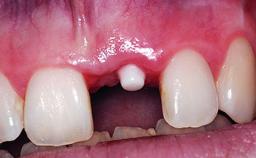

A 32-year-old female Caucasian patient with a compromised maxillary right central incisor was referred to us by a general dentist. Her chief complaints were discomfort and mobility of tooth 11 with unsatisfactory esthetics due to discoloration. The patient reported a previous trauma, some years earlier, as the origin of pathology on the afflicted tooth. Anamnesis was negative for any other dental or periodontal pathology in the remaining dentition. The patient did not take any medication and reported to be a light smoker (5–10 cigs/day). She had high esthetic expectations of her treatment. The extraoral examination revealed a high smile line with full exposure of her maxillary teeth and surrounding soft tissue in the area between the second premolars.

Prosthesis Type FDP

Provisional Implant-Supported Prosthesis Prosthodontic margin > 3 mm apical to mucosal margin Prosthodontic margin > 3 mm apical to mucosal margin

Interim Prosthesis during Healing Fixed Fixed